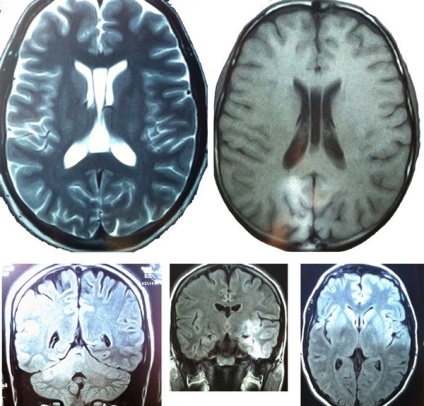

Această condiție este diagnosticată la copii printr-o examinare cu ultrasunete a capului.

măsuri de diagnosticare

Diagnosticul sindromului hidrocefalie foarte precis cu hipertensiune arterială știu cu adevărat dacă ventriculul cerebral a crescut la sugari, nu este ușor. Aplicarea cele mai noi metode de diagnostic este imposibil să se stabilească un diagnostic precis, în care sindromul conduce la faptul că în curs de dezvoltare o ușoară extensibilitate a sistemului ventricular o mică zonă a creierului copilului, sau 3 ventriculul, situat in zona a creierului extins, si pot sa apara dilatarea ventriculului stâng, este situat în creierul unui copil.

Parametrii de diagnosticare sunt considerate un nou-nascut circumferinta capului reflexelor zona de activitate. Celelalte diagnostic includ:

- Examinarea oftalmologică a fundului de ochi;

- sondaj neurosonographic pentru a vedea ce a crescut ventricul anumită parte a creierului a nou-născutului;

- exploatație tomografia computerizată și RMN-ul poate ajuta la determinarea exact ceea ce, poate e ușor dilatarea ventriculelor laterale ale copilului;

- studiu de puncție lombară, care determină gradul de presiune de lichid cefalorahidian. Această metodă este corectă, fiabilă.